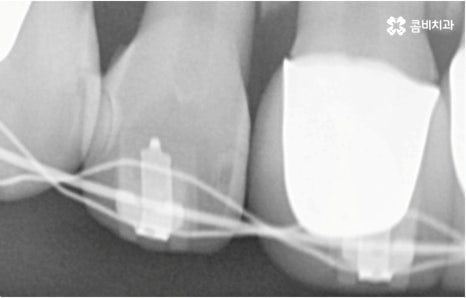

관리의 측면에서 교합이 맞지 않고 치열이 똑바르지 않으면 음식물 찌꺼기가 잘 끼고 잇몸이 붓기 쉽기 때문에 교정 치료가 필요할 수도 있습니다. 씹기가 어렵고 안면비대칭이나 턱관절 통증을 유발하는 등 심각한 부정교합의 경우 기능적으로도 필요하지만 약간 삐뚤어지거나 치아 사이가 벌어진 경우 심미적으로도 한 번쯤 교정 치료를 생각해 보셨을 텐데요, 가격이나 기간, 나이 등 여러 가지 부분이 신경쓰여서 막상 시작하기에 부감을 느끼고 계셨다면 먼저 명동치과 에 내원하셔서 자신에게 필요한 교정 치료가 어떤 것인지 알아보시면 좋을 거예요. 골격적인 원인이 크지 않고 정도가 심하지 않다면 환자분들의 상황에 따라 부분 교정으로 보다 짧고 간편하게 진행하는 경우도 있으니 3D CT 와 같이 정밀 검진 기계를 갖춘 치과에서 숙련된 의료진에게 검진 및 상담부터 받아보시길 권유드리고 있습니다.

임플란트와 교정 치료 역시 사후 관리를 철저하게 해 주는 것이 보다 오랜 기간 동안 건강하게 치아를 사용하기 위한 필수 요소이므로 주기적인 검진 및 스케일링 치료, 그리고 평상시에 명동치과 에서 말씀드리는 주의 사항을 잘 지키는 것에 대해서 늘 염두에 두시길 바라고 있어요.